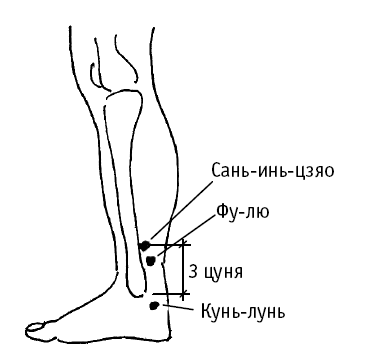

Фу-лю («возвратное стремительное течение») расположена у переднего края пяточного сухожилия.

Используется при бессоннице, сердцебиении, неустойчивых эмоциональных состояниях.

Воздействие на точку полезно также: при болезнях пищеварительной системы (боль в животе, вздутие живота, урчание в животе, жар в желудке); при воспалении горла и носовых кровотечениях; при отеке нижних конечностей; при болях в позвоночнике, пояснице и ногах; при мастопатиях и маточных кровотечениях.

Сань-инь-цзяо («пересечение трех каналов») расположена на 3 цуня выше лодыжки, у заднего края поверхности большеберцовой кости.

Точка используется при болях в эпигастральной области, рвоте, поносе, отрыжке, вздутии живота.

Дополнительный эффект от воздействия на точку: восстановление двигательной функции и уменьшение болей в тазобедренном суставе, голени и голеностопном суставе; лечение бессонницы, головной боли; лечение гинекологических заболеваний (нарушение менструального цикла, дисфункциональные кровотечения, бели, бесплодие, выпадение матки, маститы); лечение импотенции.

Фу-лю («возвратное стремительное течение») расположена у переднего края пяточного сухожилия.

Точка используется при болях в животе, вздутии, урчании в животе, ощущении жара в желудке, при изжоге.

Воздействие на точку полезно также: при болезнях пищеварительной системы (боль в животе, вздутие живота, урчание в животе, жар в желудке); при воспалении горла и носовых кровотечениях; при отеке нижних конечностей; при болях в позвоночнике, пояснице и ногах; при мастопатиях и маточных кровотечениях.

Фу-лю («возвратное стремительное течение») расположена у переднего края пяточного сухожилия.

Используется при бессоннице, сердцебиении, неустойчивых эмоциональных состояниях.

Воздействие на точку полезно также: при болезнях пищеварительной системы (боль в животе, вздутие живота, урчание в животе, жар в желудке); при воспалении горла и носовых кровотечениях; при отеке нижних конечностей; при болях в позвоночнике, пояснице и ногах; при мастопатиях и маточных кровотечениях.

Сань-инь-цзяо («пересечение трех каналов») расположена на 3 цуня выше лодыжки, у заднего края поверхности большеберцовой кости.

Точка используется при болях в эпигастральной области, рвоте, поносе, отрыжке, вздутии живота.

Дополнительный эффект от воздействия на точку: восстановление двигательной функции и уменьшение болей в тазобедренном суставе, голени и голеностопном суставе; лечение бессонницы, головной боли; лечение гинекологических заболеваний (нарушение менструального цикла, дисфункциональные кровотечения, бели, бесплодие, выпадение матки, маститы); лечение импотенции.

Фу-лю («возвратное стремительное течение») расположена у переднего края пяточного сухожилия.

Точка используется при болях в животе, вздутии, урчании в животе, ощущении жара в желудке, при изжоге.

Воздействие на точку полезно также: при болезнях пищеварительной системы (боль в животе, вздутие живота, урчание в животе, жар в желудке); при воспалении горла и носовых кровотечениях; при отеке нижних конечностей; при болях в позвоночнике, пояснице и ногах; при мастопатиях и маточных кровотечениях.